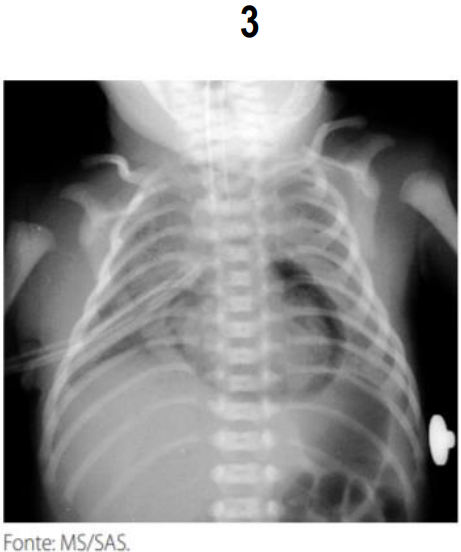

A radiografia de tórax é o exame de eleição para o diagnóstico das várias formas de SEAr. É fundamental, também, para a determinação do tamanho e da extensão da coleção de ar e da coexistência de outras entidades que possam facilitar ou perpetuar o escape de ar, além de permitir o acompanhamento evolutivo e avaliar a eficácia da terapêutica adotada. Na grande maioria dos casos o aspecto radiológico é típico, sendo possível definir o diagnóstico com relativa facilidade. Analise as imagens radiológicas com sinais patognomônico e assinale a alternativa da doença associada